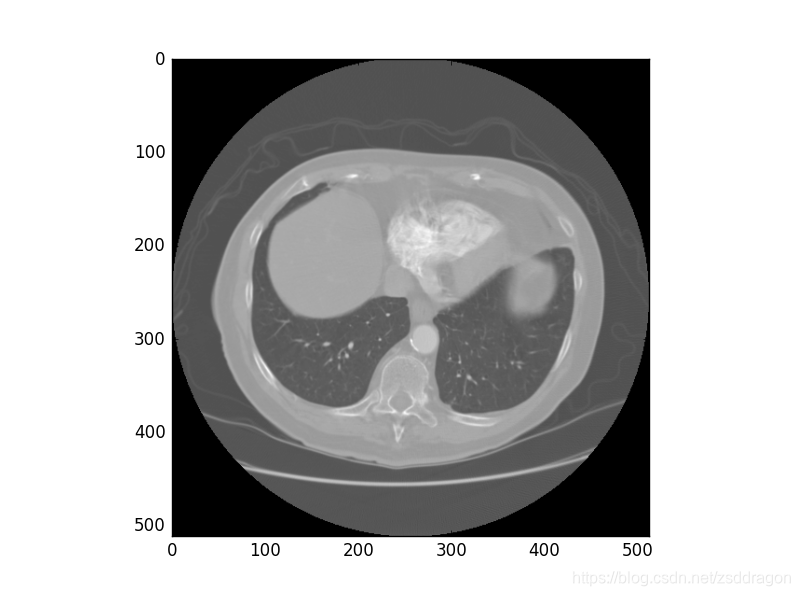

数据显示成灰度图的结果如下:

本文详细介绍了DICOM(Digital Imaging and Communications in Medicine)格式,它是医学图像和信息的国际标准,广泛应用于放射医疗等领域。DICOM文件包含患者信息、设备详情等,并通过DICOM Tag组织数据。文章还探讨了如何使用Python获取和解析DICOM文件的关键信息,包括Patient、Study、Series和Image四类信息,并展示了图像数据的灰度表示。